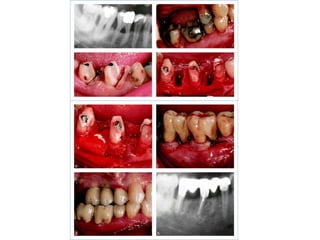

TREATMENT PROCEDURES  Group (H): 1  -  Endodontic treatment. 2  -  Custom-made gold posts & composite build-ups. 3  -  Root resection & extraction of the mesial root.  4  -  The extraction site was filled with xenograft and autologous bone and covered with resorbable membrane.  5  -  FPD included the 2 nd  premolar.  When both molars were treated, FPD included 2 nd  1 st  molar and premolar.

TREATMENT PROCEDURES  Group (I): 1  -  Atraumatic extraction. 2  -  Socket preservation by the use of nonresorbable dPTFE membrane. 3  -  Implants were placed 8 months after extraction. 4  -  Final restorations were delivered 6 months after implant placement.